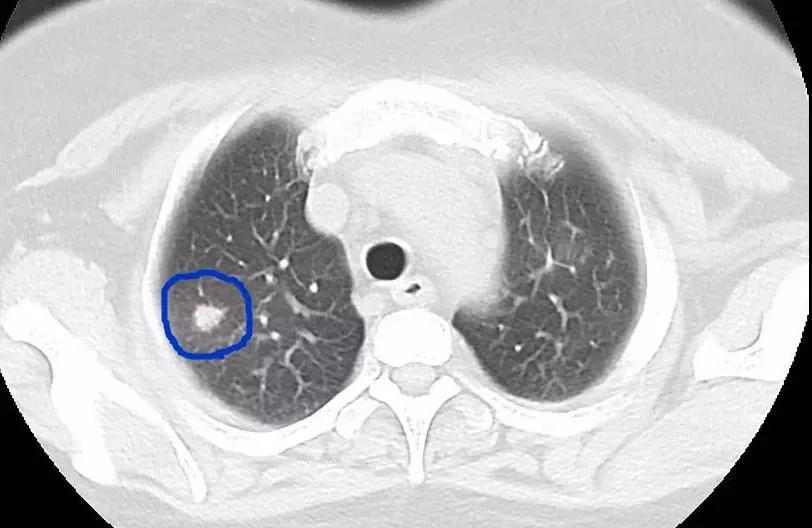

近日,深圳一家三口品尝了美味的醉蟹1个月后,先后出现了发热、腹痛、干咳等症状,他们到医院检查后,发现血常规中嗜酸性粒细胞明显升高,随即进行进一步的寄生虫抗体、CT等检查,最终三人均被确诊为“肺吸虫病”。

并殖吸虫寄生在肺部,常会引起咳嗽、胸痛、咳铁锈色痰等;虫体在腹腔脏器间移行,引起腹痛、腹泻、恶心、呕吐等症状,侵犯肝脏可致肝功能异常;如果虫体侵入大脑,更会出现头痛、头晕、癫痫、感觉异常等;此外,也可表现为皮下结节或包块。